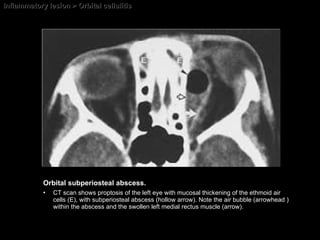

Inflammatory lesion > Orbital cellulitis Orbital subperiosteal abscess.   CT scan shows proptosis of the left eye with mucosal thickening of the ethmoid air cells (E), with subperiosteal abscess (hollow arrow). Note the air bubble (arrowhead ) within the abscess and the swollen left medial rectus muscle (arrow).